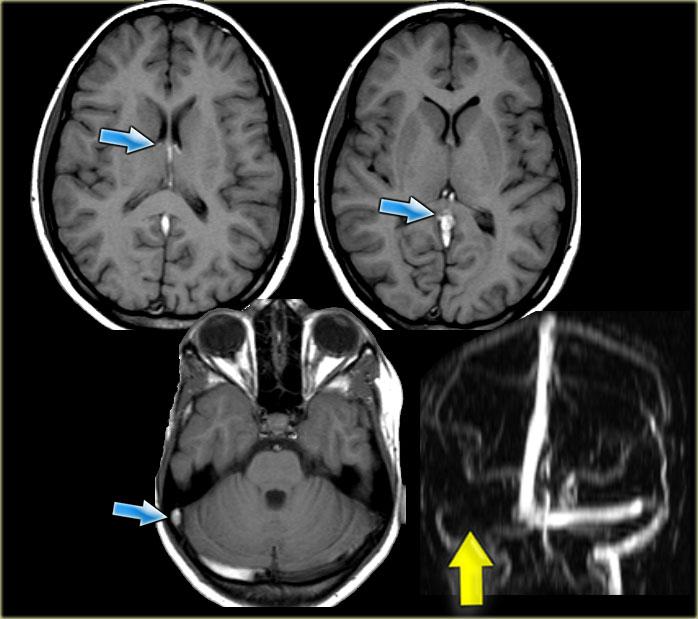

Huyết khối tĩnh mạch não sâu

Biểu hiện lâm sàng của huyết khối hệ thống tĩnh mạch não sâu là rối loạn chức năng nghiêm trọng của gian não, biểu hiện bằng hôn mê và rối loạn vận nhãn cùng phản xạ đồng tử.

Thông thường, tình trạng này dẫn đến tiên lượng xấu.

Tuy nhiên, cũng tồn tại các thể bán phần không có giảm mức độ ý thức hay dấu hiệu thân não, có thể dẫn đến chẩn đoán nhầm ban đầu.

Huyết khối hệ thống tĩnh mạch não sâu là một tình trạng thường bị bỏ sót khi triệu chứng nhẹ và cần được nghi ngờ nếu bệnh nhân là phụ nữ trẻ, nếu các tổn thương nằm trong hạch nền hoặc đồi thị, đặc biệt khi chúng xuất hiện hai bên.

Bên trái là hình ảnh của một bệnh nhân bị huyết khối tĩnh mạch não sâu.

Lưu ý các vùng nhồi máu hai bên ở hạch nền.

Tiếp tục.

Không quan sát thấy khoảng trống dòng chảy (flow void) tại các tĩnh mạch não trong, xoang thẳng và xoang ngang phải (mũi tên xanh).

Trên hình MRA, xoang ngang phải không được hiển thị.